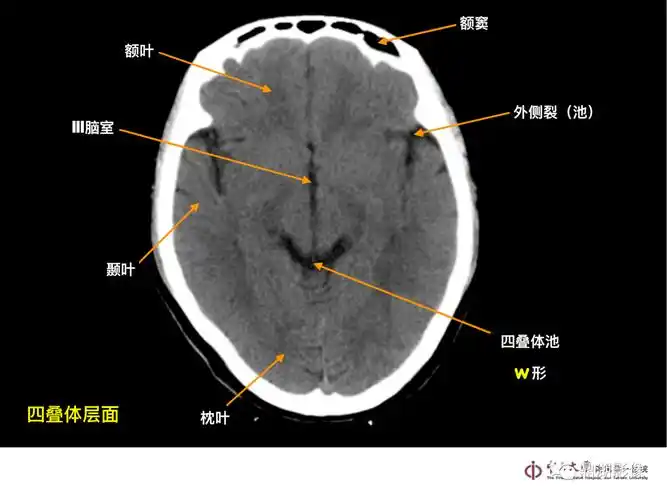

颅脑ct的正常解剖